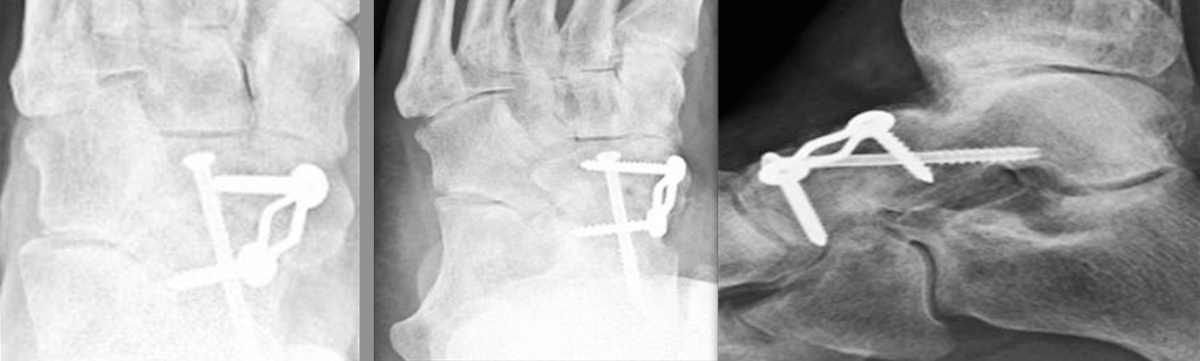

This led to the development of the locking compression plate, which has the ability to preserve the blood supply to bone by reducing periosteal stripping. The traditional plating techniques provided stability by compressing the plate to the bone surface with the screws achieving bicortical purchase as the second point of fixation. However, locking compression plate technology features unicortical locking screws that can be an “internal fixator” that can act as a bridge over compromised bone.8

One of the benefits of locking plates is their ability to be “bridge plates,” whereby they provide excellent axial and angular stability, preserve fragmentary blood supply, and reduce the risk of loss of reduction. Indeed, surgeons do not have to contour these plates anatomically to the bone, and the plates have the potential benefit of providing superior fixation in osteoporotic bone. Indications for the use of locking plates include diaphyseal/metaphyseal fractures in osteoporotic bone, multifragmentary diaphyseal/metaphyseal fractures, osteotomies in at-risk patients (poor bone stock, revisions, etc.), articular fractures, segmental fractures with multiple patterns, and any combination of the above.9

Another advancement in the development of locking plate technology is the addition of polyaxial or variable axial screw holes in the plate. This becomes extremely valuable when a surgeon is addressing a periarticular fracture, especially one that involves significant comminution or damage to the soft tissue envelope. These plates were designed to improve angular stability by allowing variable screw trajectory to the plate, thereby increasing the probability that the screw will be able to purchase good bone while avoiding articulating surfaces.